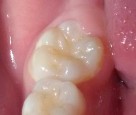

Bệnh nhân: Ng. Minh T. 9 tuổi. Răng 36, mã BA 13519/17

Sau ba tháng. ICDAS:2; Di: 22 | Sau 12 tháng. ICDAS:0; Di: 09 | Sau 18 tháng. ICDAS:0; Di: 05 |